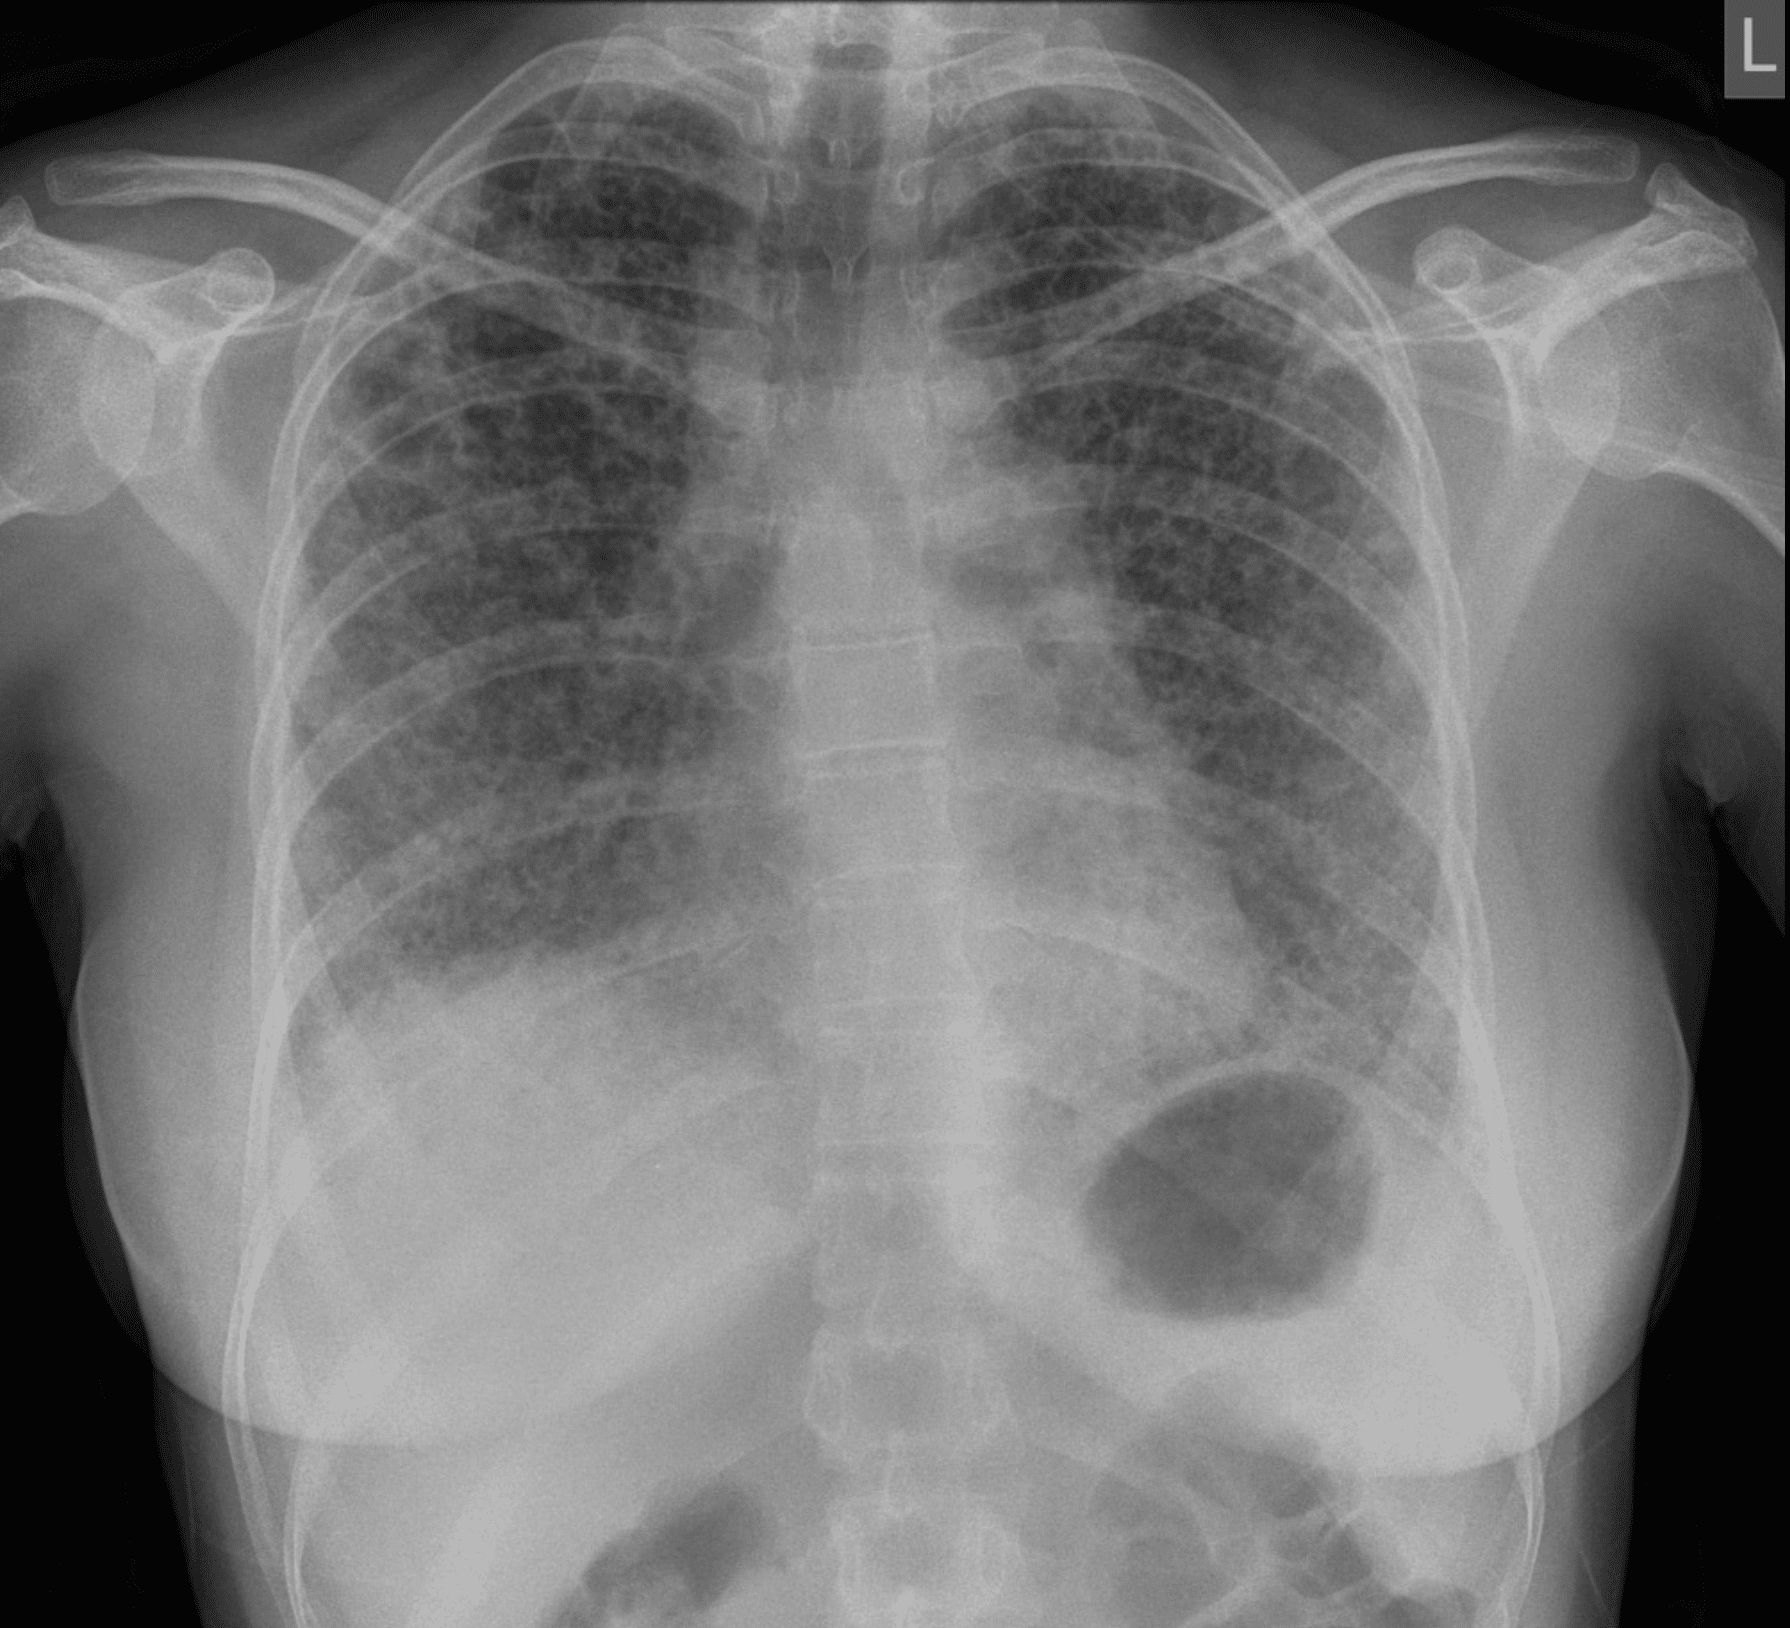

| Modality | Findings |

|---|---|

| CXR | Basal reticular/nodular opacities, pleural plaques, “shaggy heart” sign |

| HRCT | Subpleural linear opacities, parenchymal bands, honeycombing, plaques |